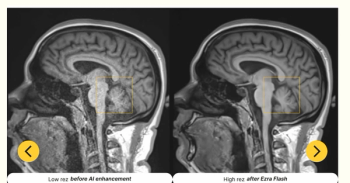

The updated software reportedly enables a threefold improvement in MRI scan time and enhanced image sharpness.

The updated AI-enabled software reportedly facilitates enhanced MRI imaging of the brain, abdomen, and pelvis.